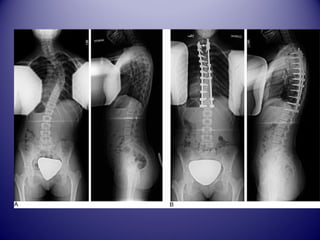

LLAA SSCCOOLLIIOOSSEE CCHHEEZZ

LL’’AADDOOLLEESSCCEENNTT

BBIILLAANN

RRAADDIIOOLLOOGGIIQQUUEE

DE FACE ET DE PROFIL !!!

Mesure ddeess ccoouurrbbuurreess::

AAnnggllee ddee CCoobbbb

TEST ddee rréédduuccttiibbiilliittéé

((BBeennddiinngg))

Test ddee RRiisssseerr ++ AAggee

OOsssseeuuxx

5A 12 A

Traitement ddee llaa ssccoolliioossee::

PPrriinncciippee

 AArrrrêêtteerr llaa pprrooggrreessssiioonn ddee llaa ccoouurrbbuurree

((ccoorrsseettss))

 RRéédduuiirree llaa ccoouurrbbuurree ((PPllââttrree))

 CCoorrrriiggeerr llaa ccoouurrbbuurree ((CChhiirruurrggiiee))

 ÉÉvviitteerr lleess ccoommpplliiccaattiioonnss ttaarrddiivveess ((ccaarrddiioo--

ppuullmmoonnaaiirree,, nneeuurroollooggiiqquuee))

 AAmméélliioorreerr ll''eesstthhééttiiqquuee ((ggiibbbboossiittéé))

Les corsets oorrtthhooppééddiiqquueess

Le ccoorrsseett oorrtthhooppééddiiqquuee

 SSii ccoouurrbbuurree ssuupp 2200°° eett aavvaanntt RRiisssseerr 33

 FFrreeiinnee oouu aarrrrêêttee llaa pprrooggrreessssiioonn ddeess

ssccoolliioosseess

 PPoorrtt nnooccttuurrnnee eett ddiiuurrnnee !!!!!! ((ssaauuff BBeennddiinngg

ccoorrsseett))

 2233HH//224HH aauu ddéébbuutt eett 1166HH//224HH eenn vviitteessssee ddee

ccrrooiissiièèrree

 JJuussqquu’’àà RRiisssseerr 4,,55

 SSeevvrraaggee pprrooggrreessssiiff

Traitement cchhiirruurrggiiccaall

Indication tthhéérraappeeuuttiiqquuee

 SSccoolliioossee dduu nnoouurrrriissssoonn:: ppaass dd’’iinnddiiccaattiioonn ssaauuff ssii

rriissqquuee dd’’éévvoolluuttiivviittéé

 SSccoolliioossee iinnffaannttiillee eett jjuuvvéénniillee::

iinnddiiccaattiioonn cchhiirruurrggiiccaallee ffrrééqquueennttee ..

CCoorrsseett ddee MMiillwwaauukkeeee eenn ppoorrtt nnooccttuurrnnee ssii <<3300°°

eett 2233HH//224HH ssii >>400°°

 SSccoolliioossee ddee ll’’aaddoolleesscceennccee::

>>2200°° CCoorrsseett mmoonnooccooqquuee

((CChheenneeaauu,,TTLLSSOO,,LLyyoonnnnaaiiss,,BBoossttoonn,,CChhaarrlleessttoonn……

))

>> 455°° AArrttrrooddèèssee vveerrttéébbrraallee ppoossttéérriieeuurr